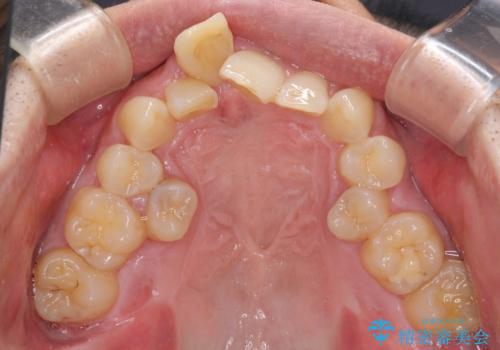

通常では速やかにオールセラミッククラウンにて補綴治療を行うのですが、デコボコしている歯列も気になっていたため、事前に矯正治療を行うこととしました。

上顎歯列の叢生が著しかったため、上顎左右第一小臼歯2本を抜歯し、目立たないワイヤー装置にて治療を進めることとしました。